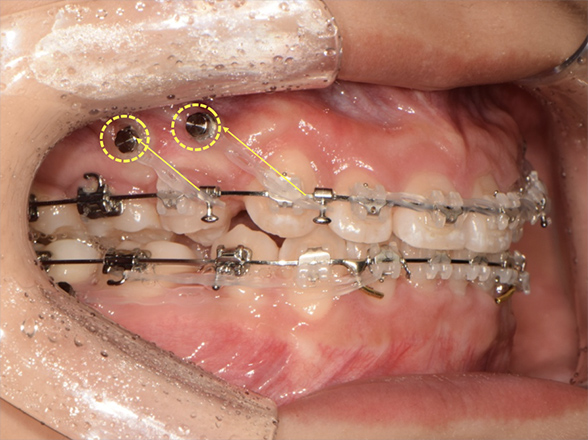

비수술 턱교정의 핵심

Miniscrew 를 이용한 3차원적 치아 이동

세브란스병원 치과교정과의 고유 테크닉

Total Arch Intrusion (전치열 함입)